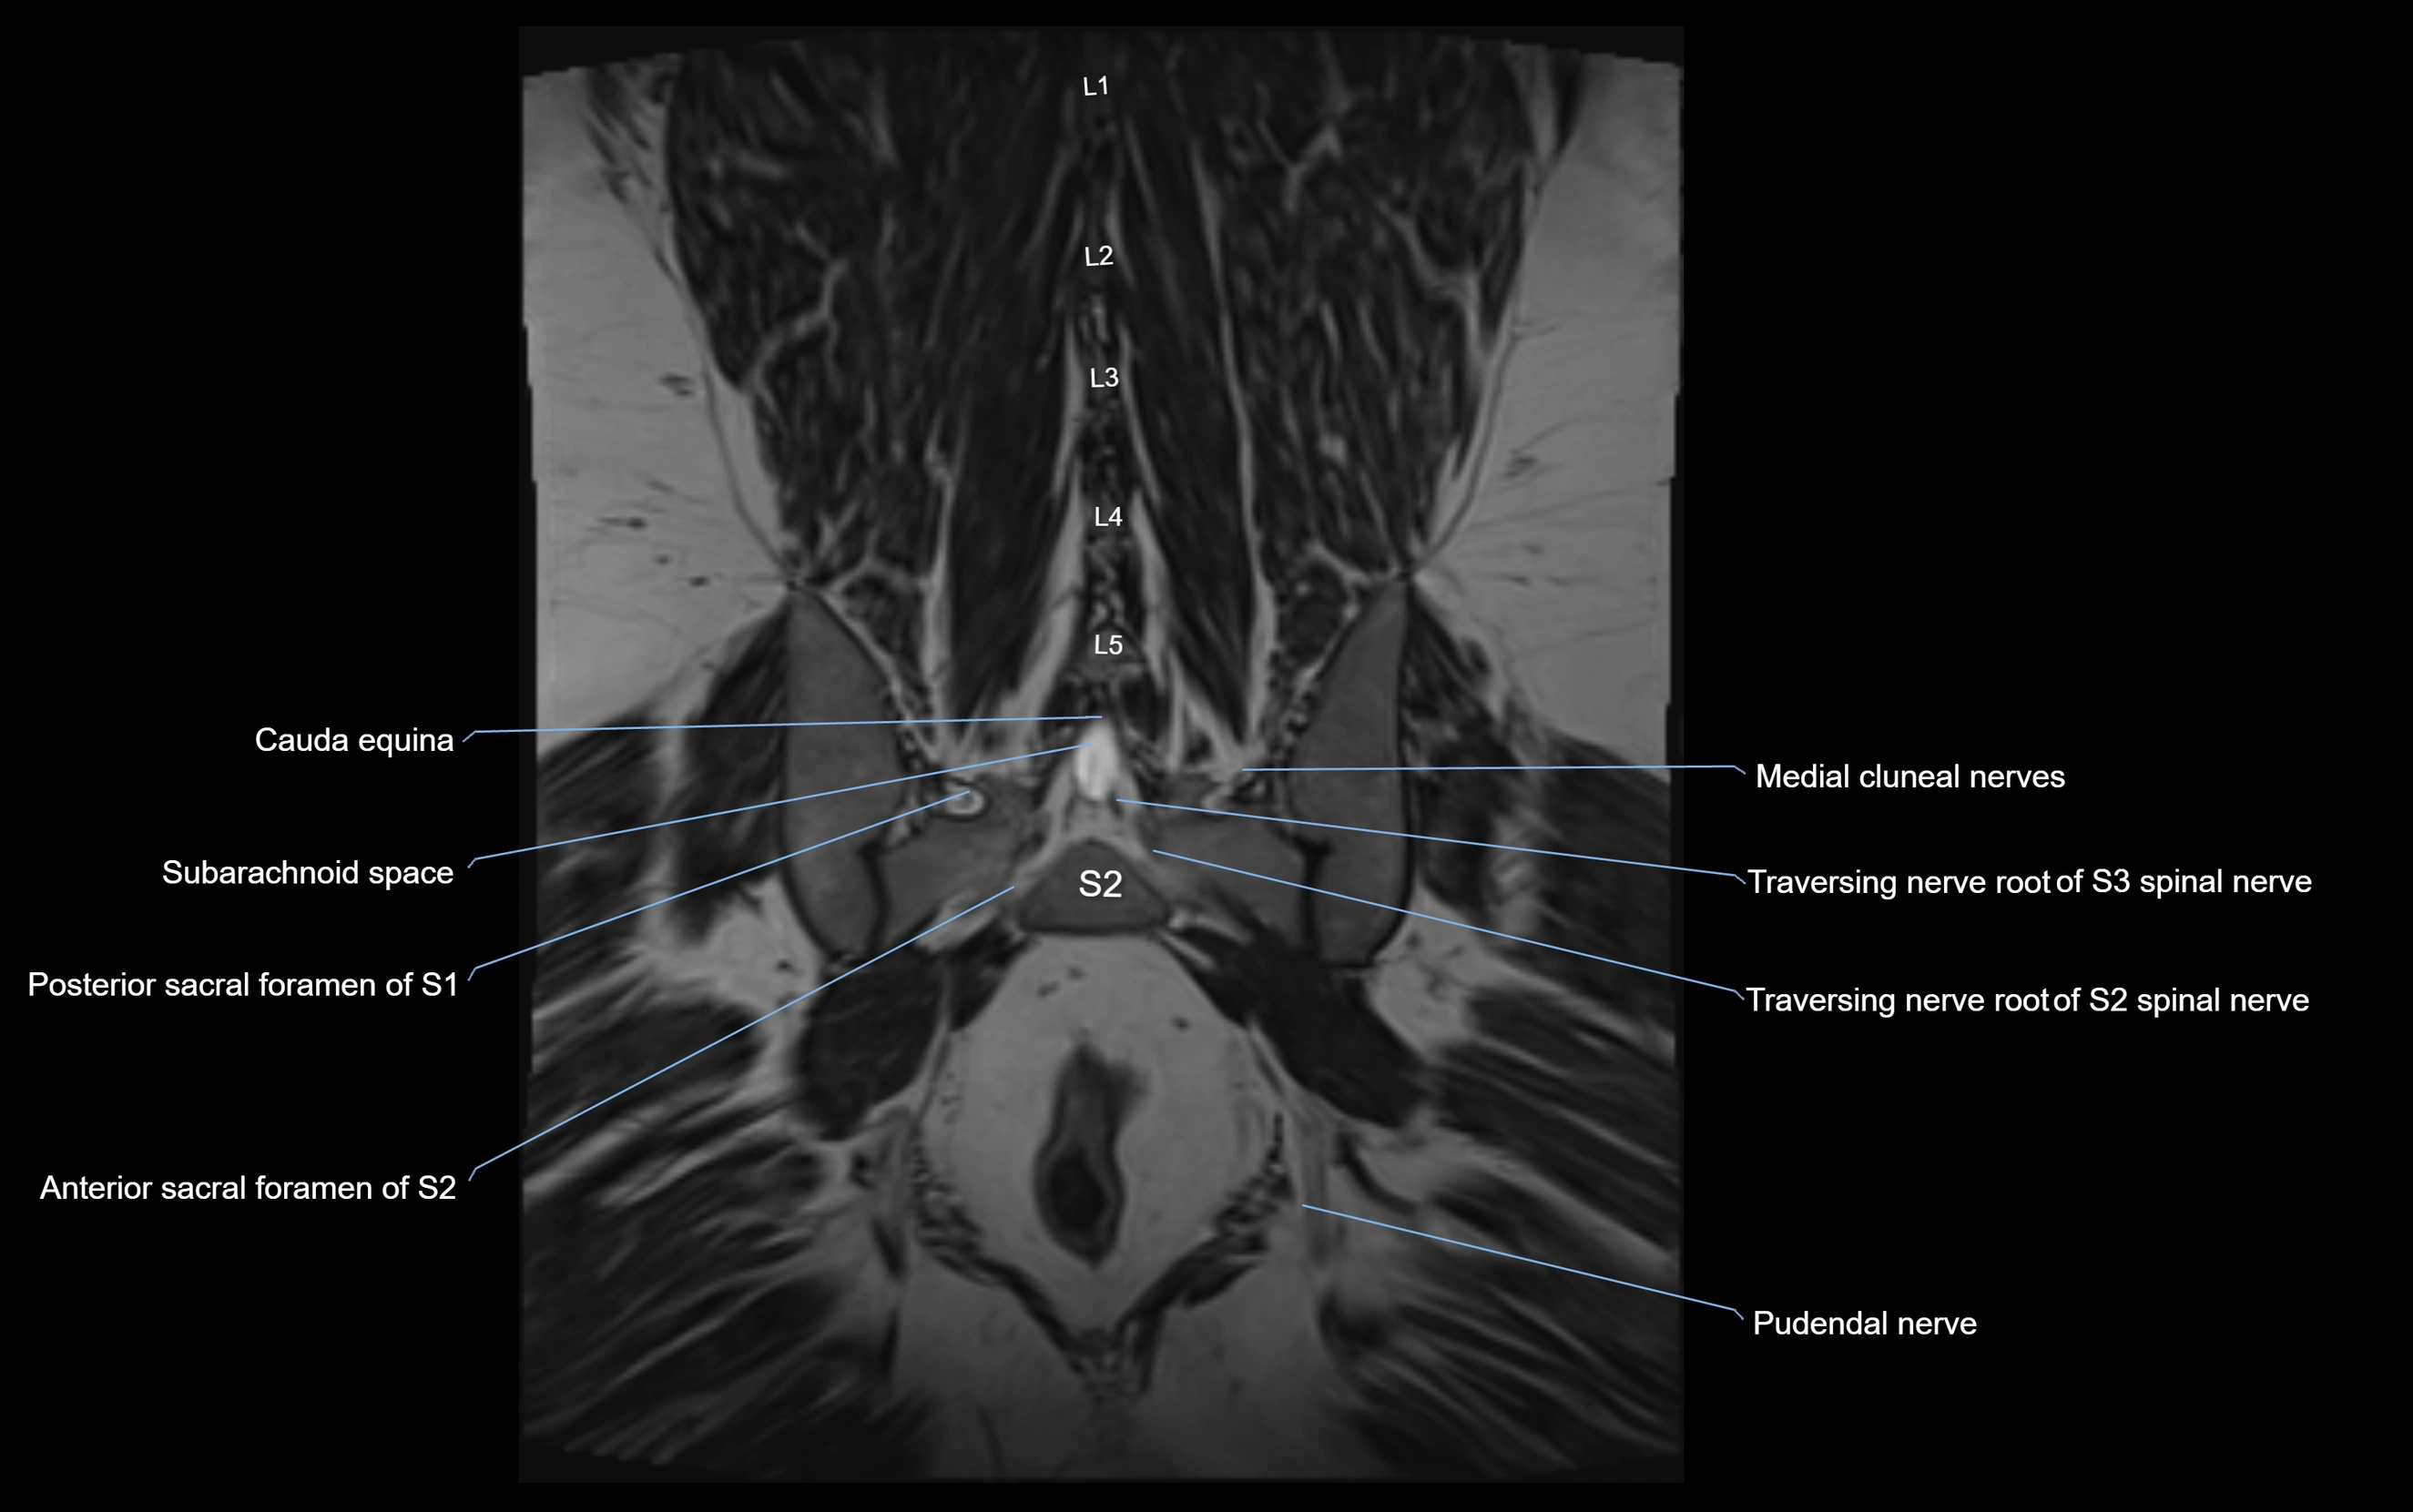

MRI image

image